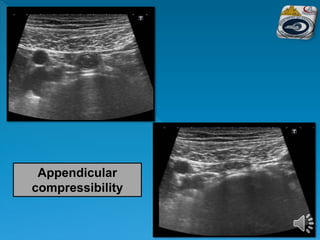

 Beginning at the right anterior superior iliac

spine and moving medially to the edge of the

rectus muscles in a sagittal plane, the right

common iliac vessels are identified.

 Rotating anticlockwise to a transverse plane

and moving cranially, the first bowel loop

crossing from medial to lateral is identified as

the terminal ileum.

 This is followed to the ileocaecal valve and

caecum.

 The base of the appendix can be identified at

the deep margin of the caecum where the three

taenia coli meet

Appendicular

compressibility